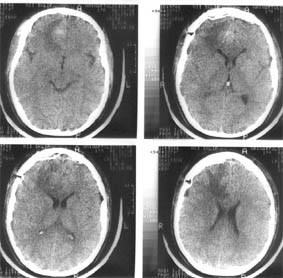

Компьютерная томография (КТ) и магнитно-резонансная томография (МРТ) — наиболее важные диагностические исследования при инсульте. КТ в большинстве случаев позволяет чётко отдифференцировать «свежее» кровоизлияние в мозг от других типов инсультов, МРТ предпочтительнее для выявления участков ишемии, оценки распространённости ишемического повреждения и пенумбры. Также с помощью этих исследований можно выявлять первичные и метастатические опухоли, абсцессы мозга и субдуральные гематомы. Если наблюдается ригидность затылочных мышц, но отсутствует отёк диска зрительного нерва, люмбальная пункция в большинстве случаев позволит быстро установить диагноз кровоизлияния в мозг, хотя при этом сохраняется незначительный риск возникновения синдрома «вклинения» мозга. В случаях, когда есть подозрения на эмболию, люмбальная пункция необходима, если предполагается применение антикоагулянтов. Люмбальная пункция имеет также важное значение для диагностики рассеянного склероза и, кроме того, может иметь диагностическое значение при нейроваскулярном сифилисе и абсцессе мозга[36]. При недоступности КТ или МРТ необходимо выполнить эхоэнцефалографию и люмбальную пункцию.